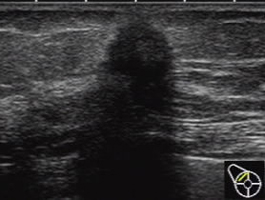

エコー検査ともいいます。マンモグラフィや視触診と組み合わせて行なわれることが多いです。超音波(人間には聞こえない音)を体に向かって当てて、臓器からの音の反射を画像にして観察する検査です。

痛みを伴わない、しこりは大きくても小さくてもよく検出される、乳腺が発達している若い人にも適している、といった長所があります。

しかし、石灰化はわからないので、マンモグラフィと組み合わせての利用が推奨されます。